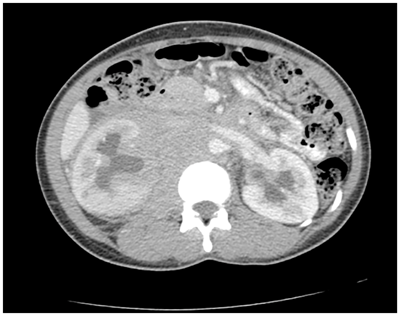

A pelvic mass and bilateral hydronephrosis was noted on ultrasound of the urinary tract. Therefore, a CT scan was arranged. The CT scan (Figure 1) demonstrated a mildly enhancing soft tissue density in the retroperitoneum engulfing the major vessels, ureters and psoas muscles. The mass extended from the diaphragmatic crus to the pelvis. There was bilateral hydronephrosis affecting the right side slightly more than the left. No lymphadenopathy was demonstrable. The features exhibited were consistent with either lymphoma or retroperitoneal fibrosis. In light of her clinical history of recent migration from Africa and her symptoms suggestive of immunosuppression, lymphoma was the more likely in this case. A high-index of suspicion was warranted for infectious causes; however, the weight loss and night sweats indicated lymphoma (B symptoms). The microcytic anaemia, low albumin and slightly elevated C-reactive protein were also suggestive of a chronic condition. Initially bilateral insertion of ureteric double J-stents was performed endoscopically to relieve the ureteric obstruction. This proceeded without complication and post-operatively her creatinine level normalized.

Figure 1 Axial view of CT scan of abdomen showing mildly enhancing soft tissue density in the retroperitoneum causing bilateral hydronephrosis.